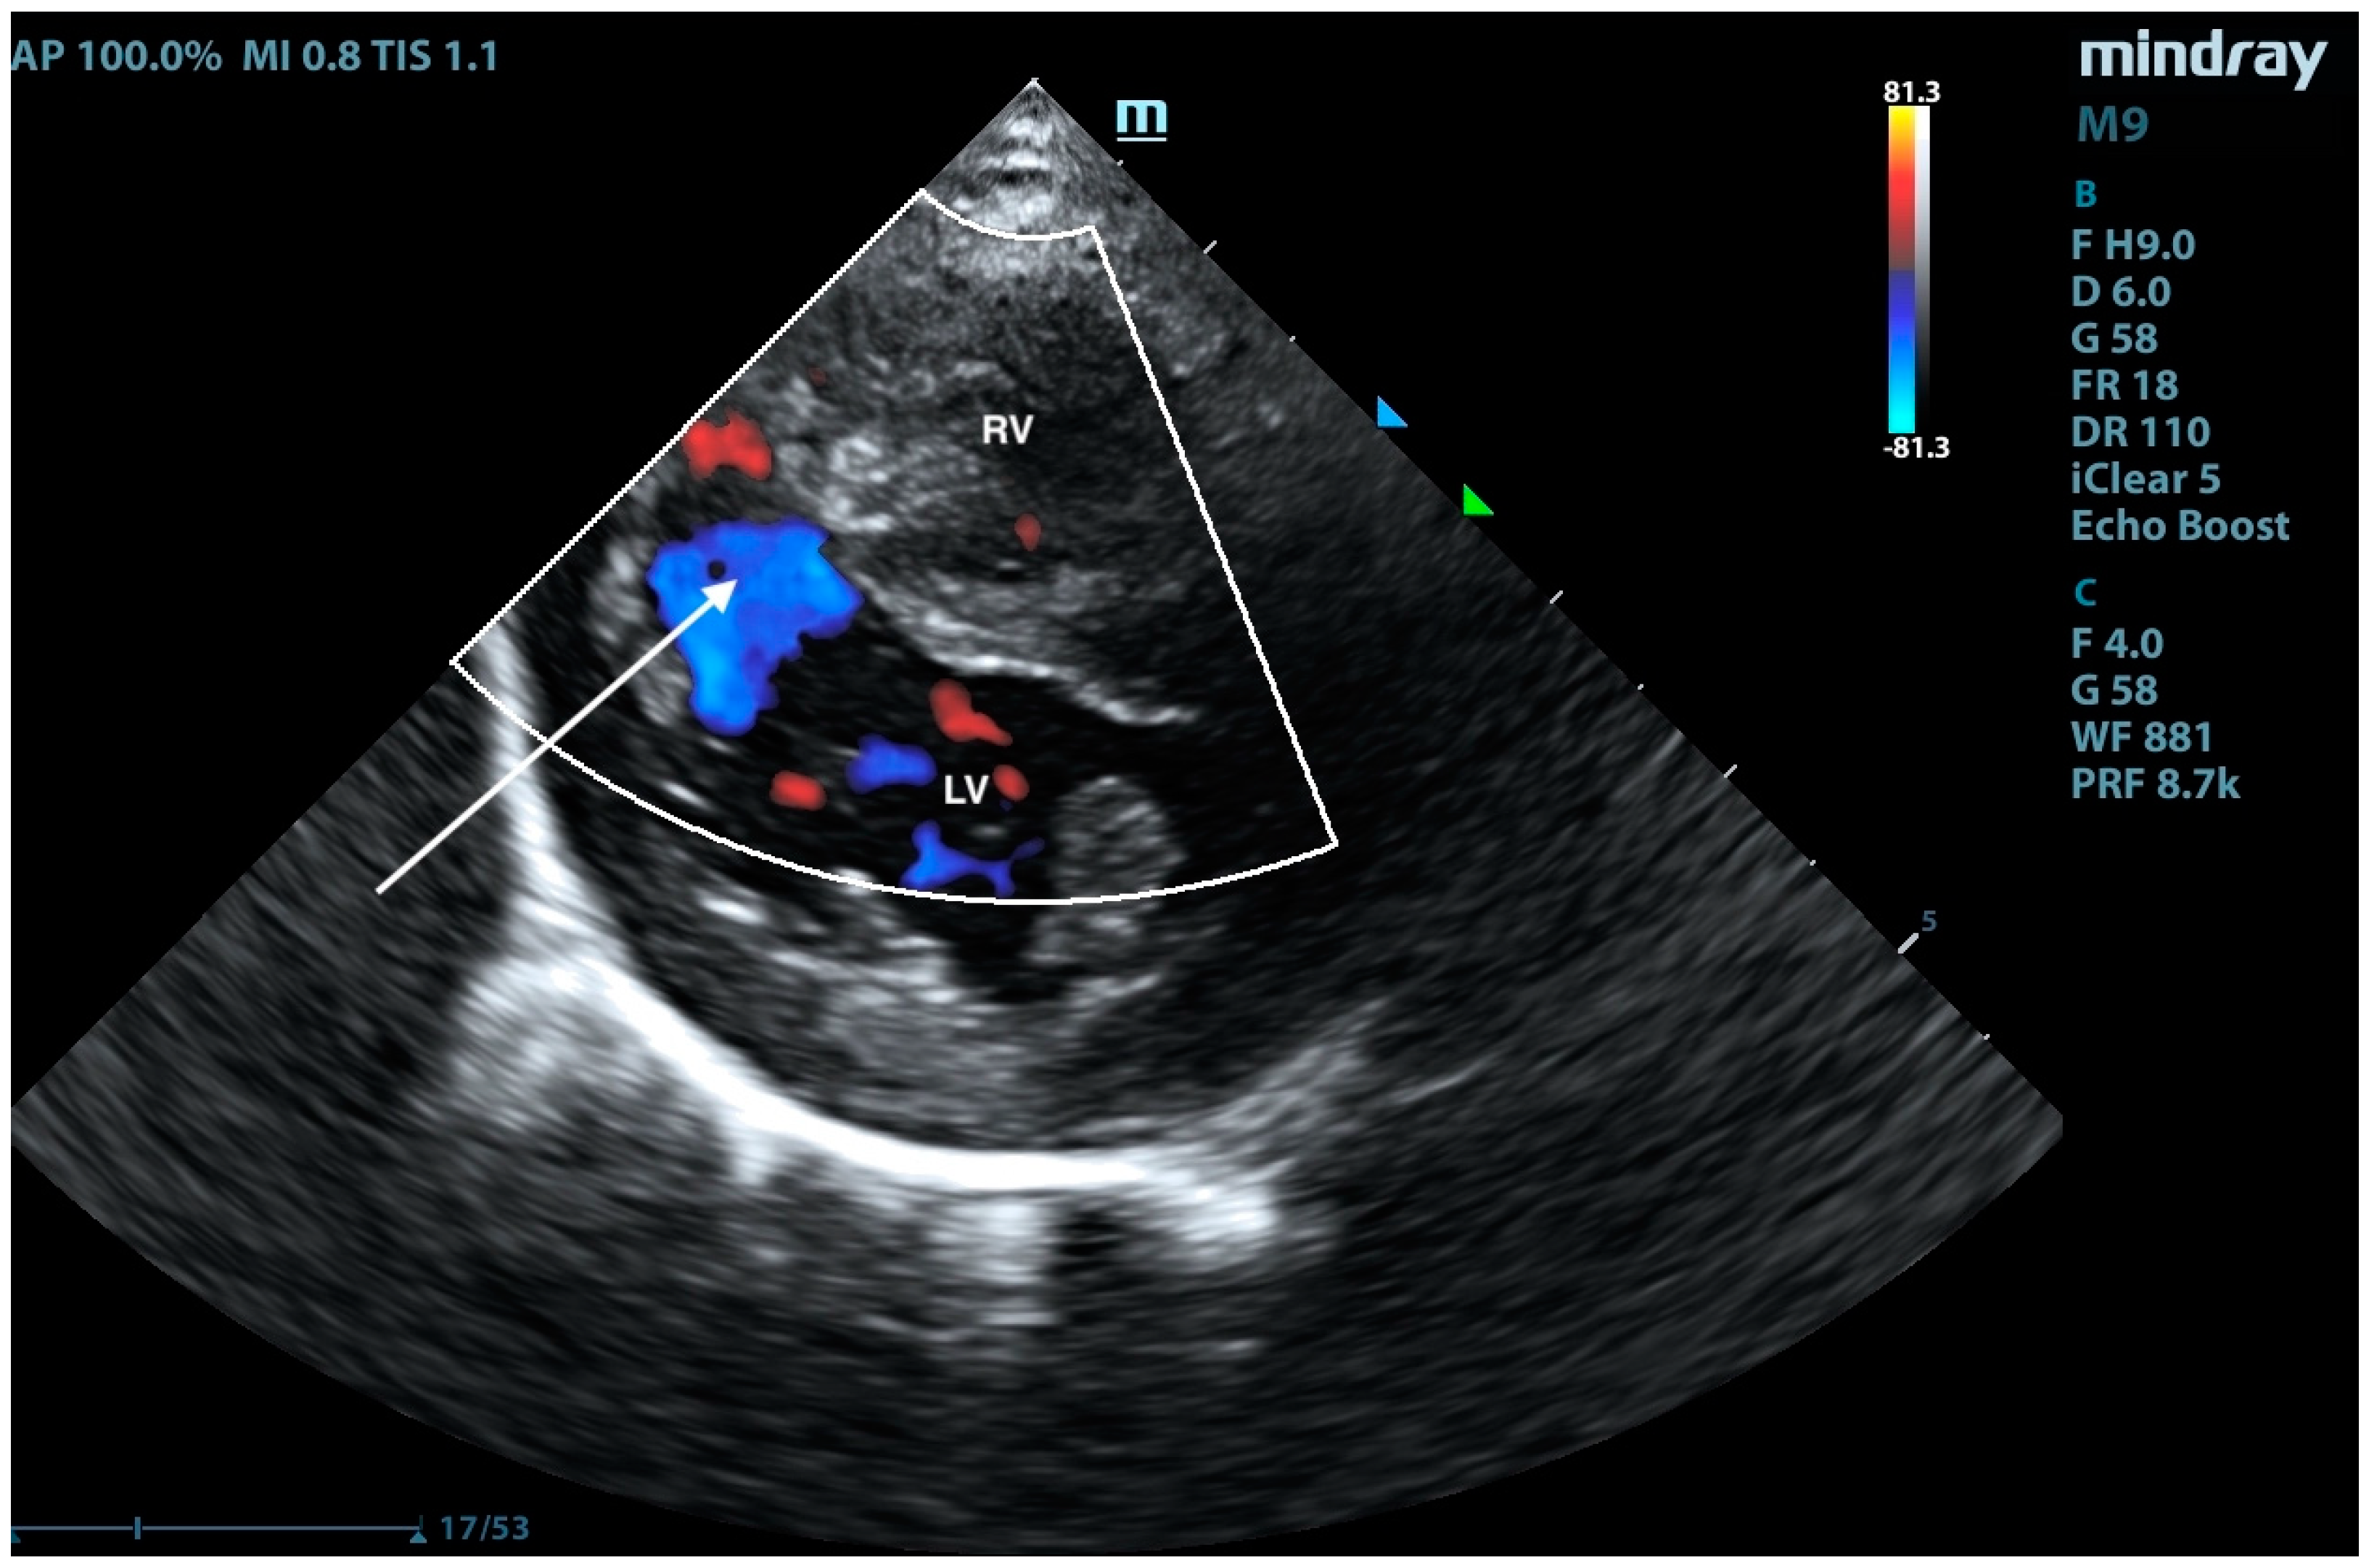

2. Case Presentation